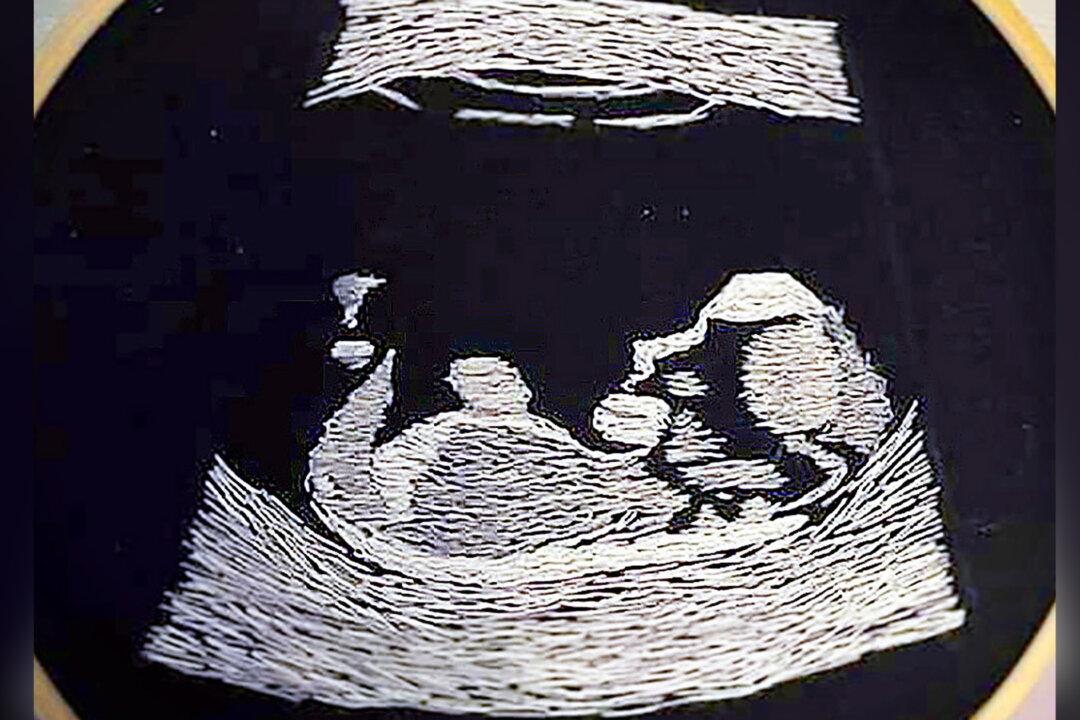

When a man who’s been blind since the age of 6 discovered he was going to become a father, he was overjoyed. But he was missing out on the experience of seeing ultrasound photos of his baby in the womb; that is, until a friend gifted him an embroidered image so he could feel for himself the shape of his unborn child.